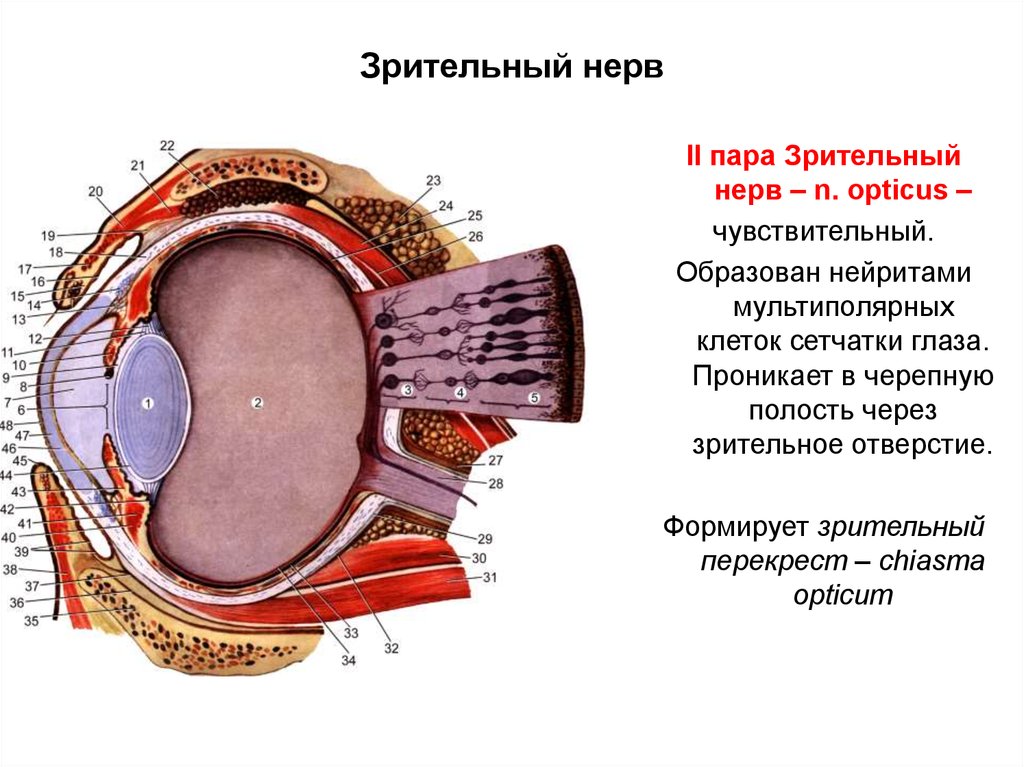

КТ-графики и изображение строения глаза